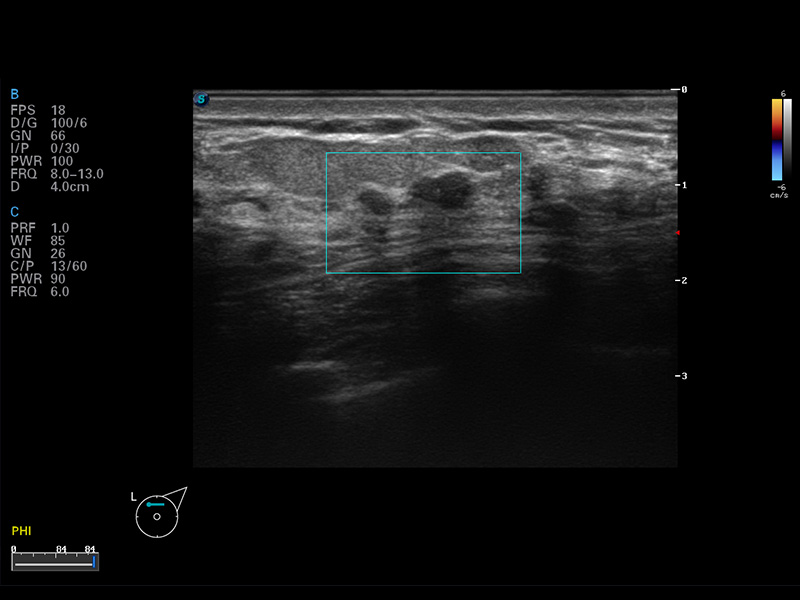

S8 EXP便携式彩色多普勒超声诊断仪是百老汇电子游戏官网研发的高端全身应用型便携彩超。高通道的VIS平台融合可视化(Visual)、智能化(Intelligent)和人性化(Smart)的特点,配以百老汇电子游戏官网自主研发生产的探头大家族,使您能够快速、准确的获得病人信息,提高工作效率的同时减轻疲劳。

μ-Scan微米成像

谐波成像

空间复合成像